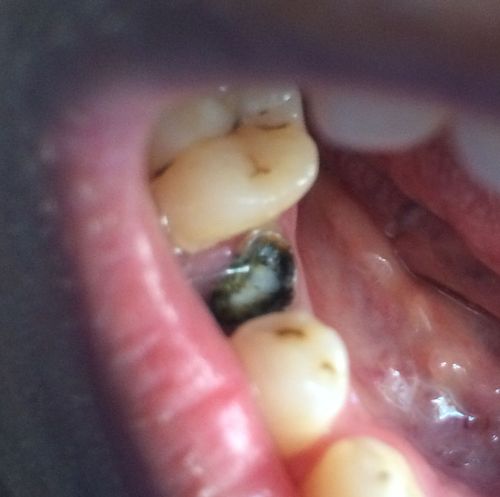

这位医生并没有想到,一次看似简单的牙根截根手术竟然会引发如此令人震惊的并发症。在手术过程中,医生小心翼翼地处理着牙根,试图将其顺利截断。就在医生以为一切都进行得很顺利的时候,牙根竟然发出了“咔嚓”的声音,折裂成了两半!医生当时的表情可想而知,惊讶得下巴都要掉到地上了。

那么,为什么那颗牙根会折裂呢?医生经过仔细的观察和分析后发现,这颗牙根的内部结构异常复杂,存在一些微小的裂纹。而在牙根截根手术过程中,由于受到了一定的力量,这些微小的裂纹逐渐扩大,最终导致了牙根的折裂。

牙根折裂的后果牙根折裂的后果可不容小觑。牙根折裂后,无法像正常情况下那样顺利进行截根手术,需要医生采取其他更复杂的治疗方式,比如拔牙。牙根折裂还可能导致周围组织的感染和疼痛,给患者带来不必要的痛苦和烦恼。